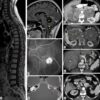

– Ung thư ống nhú (Papillary renal cell carcinoma): chiếm 10%, các tế bào u có nguồn gốc từ tế bào ống lượn xa. Vi thể: cấu trúc ống nhú được phủ bởi tế bào có kích thước nhỏ, bào tương bắt màu kiềm, với một nhân gồm ít hạt nhân tế bào không điển hình. Gel: không thấy sự khiếm khuyết của nhánh ngắn NST 3 đặc trưng của ung thư tế bào sáng. Ngược lại, có 1 trisome 7 và 1 trisome 17 (+7 ; + 17) kết hợp với sự thiếu NST Y (-Y) trong các ống tuyến nhú, thường gặp trong bệnh nhân nhiều nang thận bẩm sinh